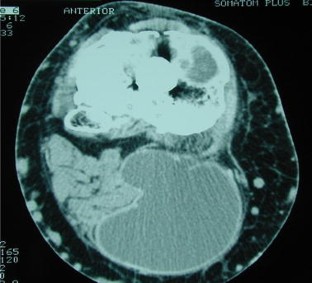

Multilobulated popliteal cyst after a failed total knee arthroplasty

Popliteal cyst is a rare finding after total knee arthroplasty (TKA), but when present, it might indicate a malfunction of the TKA related to generation of wear-particles, or loosening. We present a case of a multilobulated popliteal cyst developing in a patient 8 years after primary TKA. The cyst was associated with a mechanical prosthetic loosening. The primary complaint of the patient was pain in the posterior region of the knee. A two-stage procedure consisting of cyst excision at first, followed after 5 months by a revision TKA was performed. Intraoperatively, a darkish, multilobulated cyst with a well-defined thick wall filled with fluid containing polyethylene debris, communicating with the knee joint was found. After 3 years of follow-up, the patient was satisfied and walked without the support of a cane. The patient presented a satisfactory knee range of motion. Clinical, radiological and ultrasound investigations ruled out popliteal cyst recurrence. A dissecting popliteal cyst associated with a failed TKA should be excised because it contains polyethylene debris that constitutes an induced factor for prosthetic loosening. A two-stage procedure with quite a long time in-between, as presented in this paper, can be a useful alternative to manage such a problem, in particular in very old patients associated with other medical problems.

Fig. 2